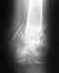

Несвежий оскольчатый перелом вертлужной впадины со смешением костных осколков. Переломовывих головки правой бедренной кости.